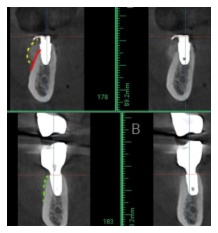

사진 1) 임플란트 식립하기에 뼈의 수평 폭이 많이 부족합니다.(5.64mm)

어금니에는 직경 5mm의 임플란트를 식립하며, 임플란트를 둘러싸는 뼈의 폭은 최소 1.5mm가 요구되기에 어금니 임플란트를 식립하려면 최소 8mm의 뼈가 필요합니다.(8=5+1.5+1.5)

따라서 뼈이식을 통해 뼈의 두께를 확보해야 하는 상황입니다.

사진 2) 뼈이식을 통해서(노란색 점선), 충분한 두께의 뼈를 만들어 냈습니다.(초록색 점선)